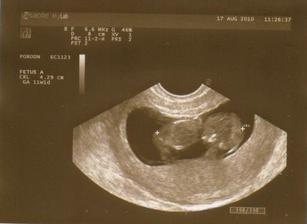

17. 8. 2010 Prvá oficiálna poradňa, bábätko má 4 cm a nádherne sa v brušku prehadzovalo